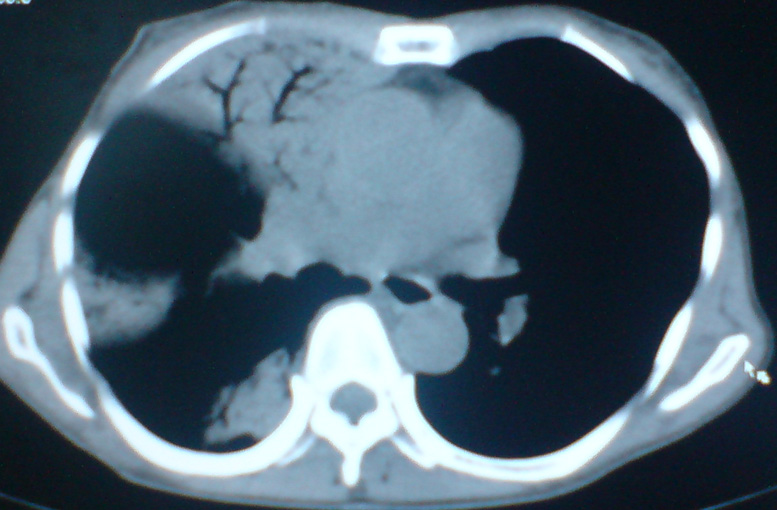

患者,女,60岁,右侧胸痛、咳嗽两个月。

不出意外的话应该是弥漫性肺泡癌。

肺泡癌?肺泡蛋白沉积症?

考虑肺炎,未除肿瘤。建议复查。